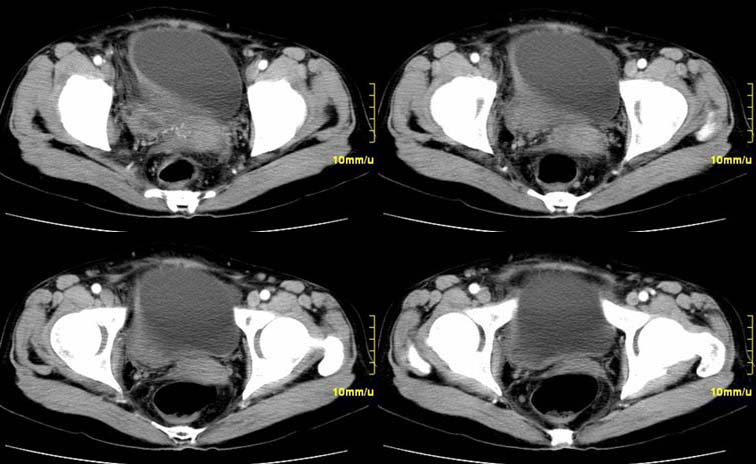

患者,52,右下腹疼痛一月,当时有发热,抗炎治疗20余天,至今仍疼痛,且有低热。

右侧附件见一肿块,边缘与周围组织分界不清,增强扫描见肿块明显强化,越到后期强化越明显,中央见坏死,内壁光整,与临近子宫壁、直肠及膀胱后壁均见炎症波及。这种厚壁肿块、内缘光整外缘模糊、增强扫描强化越后越强是附件脓肿典型的ct表现。

右侧卵巢输卵管慢性脓肿,炎症波及临近子宫、直肠及膀胱形成粘连。

病变定位在右侧附件,肿块内见有低密度灶,周围结构模糊,增强肿块实质部分明显强化,因患者起病有发烧,故首先考虑右侧附件炎性包块并脓肿形成,不除外以实质部分为主的不典型卵巢癌的可能。